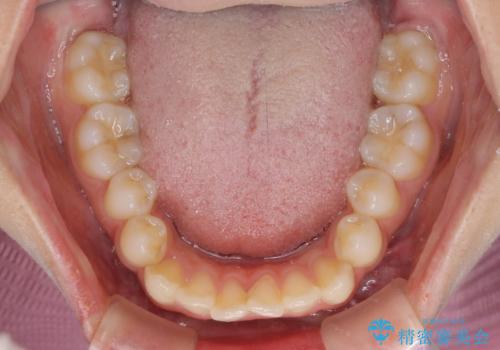

- 上下前歯のデコボコを気にして来院された患者様です。

前歯のセラミックが装着されている歯は、歯根が短くなっており、他院では抜けてしまうので矯正はできないと言われていたようです。

患者様と相談し、抜けてしまった場合にはインプラントあるいはブリッジによる補綴治療が必要となることを確認し、極力歯根に負担のかからないような仕上がりで治療を進めて行くこととしました。

デコボコを解消には、IPR(歯と歯の間を削る)をメインに歯列排列を設計し、インビザラインにて矯正治療を行うこととしました。

レントゲン写真上では、矯正治療前後で歯根長さに大きな違いはなく、抜歯を回避することができました。

上顎内側に転位している前から2番目の歯は移動が難しく、無理矢理歯根全体を動かそうと設計すると、歯肉退縮・歯髄壊死・歯根吸収といった危険性が増すため、無難なゴールにて治療を終えることとなりました。